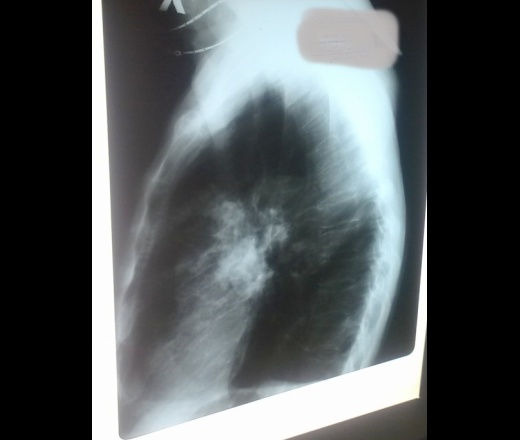

Поступил с пневмонией. Т - 37,7 и не выше, кашель, мокрота скудная, скопия экспересс- микобактерий нет, посев в процессе. Снимки сделаны косо из-за полос! Написано: 2ст. пневмония

Пролечили 10дней - контроль, и динамика вроде есть, но не дает покоя субплевральное затемнение( или затенение) слева.

Думаю туберкулезные дела?

Да туберкулез наверное, у нас часто туберкулез динамику незначительную даже на обычных а/б давал, а потом фтизиатры признавали своими

КТ однозначно. Ну а так, на вскидку, это плевральные дела.

Пневмония справа, слева осумкованный выпот.

За пневмонию. Контроль в динамике.

Не будет динамики за 10 дней при туберкулёзе.Пневмония,дальнейший контроль.

Не поленился поднял архивы- снимков увы, а КТ не спрячешь. С чего началось - 2012г. Непонятные осумкования жидкости слева, полость невнятная, но справа писал туб. Не поверили - ВК-. Лечился все же как туб, сегодня уважаемые фтизиатры заявляют о периферическом с распадом. Ну минус! Но мне кажется - туб и туб. настоятельно.

Для оценки данных КТ необходимо полное исследование в Дайком-формате. А предварительно, по фрагментам КТ: двусторонняя полисегментарная бронхопневмония в стадии неполного разрешения; эмпиема плевры слева.

По сравнению с данными КТ от 2012 и 2013 гг. выраженная положительная динамика плевральных изменений слева, но отрицательная в плане очаговых изменений в правом легком. И все же пока: двусторонняя полисегментарная бронхопневмония в стадии неполного разрешения, с реактивными изменениями костальной плевры слева на всем протяжении, преимущественно на уровне сегментов S3, S4. Дальнейшее лечение; с учетом архивных данных повтор ТВС исследований и консультаций фтизиатров; динамический КТ контроль через 1-2 месяца.

На первый взгляд сразу за онко подумал. Лимфангоит какой-то присутствует. Разрешение пневмонии и полости распада... наврядли. Поддержу мнение о туберкулезе.

Фиброзно-кавернозный.

Таки так, фиброзно-кавернозный. Какая же тут динамика пневмонии на протяжении года и с дырками в легких. Резистентная форма.

это не фиброзно-кавернозный туберкулез

Возможно ошибаюсь, но это - не предел метода (КТ). Сложность заключения изменений бронхо-легочной системы в данном случае зависит от правильной интерпритации полученных данных. Участки консолидации легочной ткани, на фоне которых прослеживаются фрагменты воздушных и измененных бронхов (симптом воздушной бронхографии), некоторыми коллегами воспринимаются как (дыры в легких - их выражения; каверны). Отсюда и высказывания о "фиброзно-кавернозном твс!?"